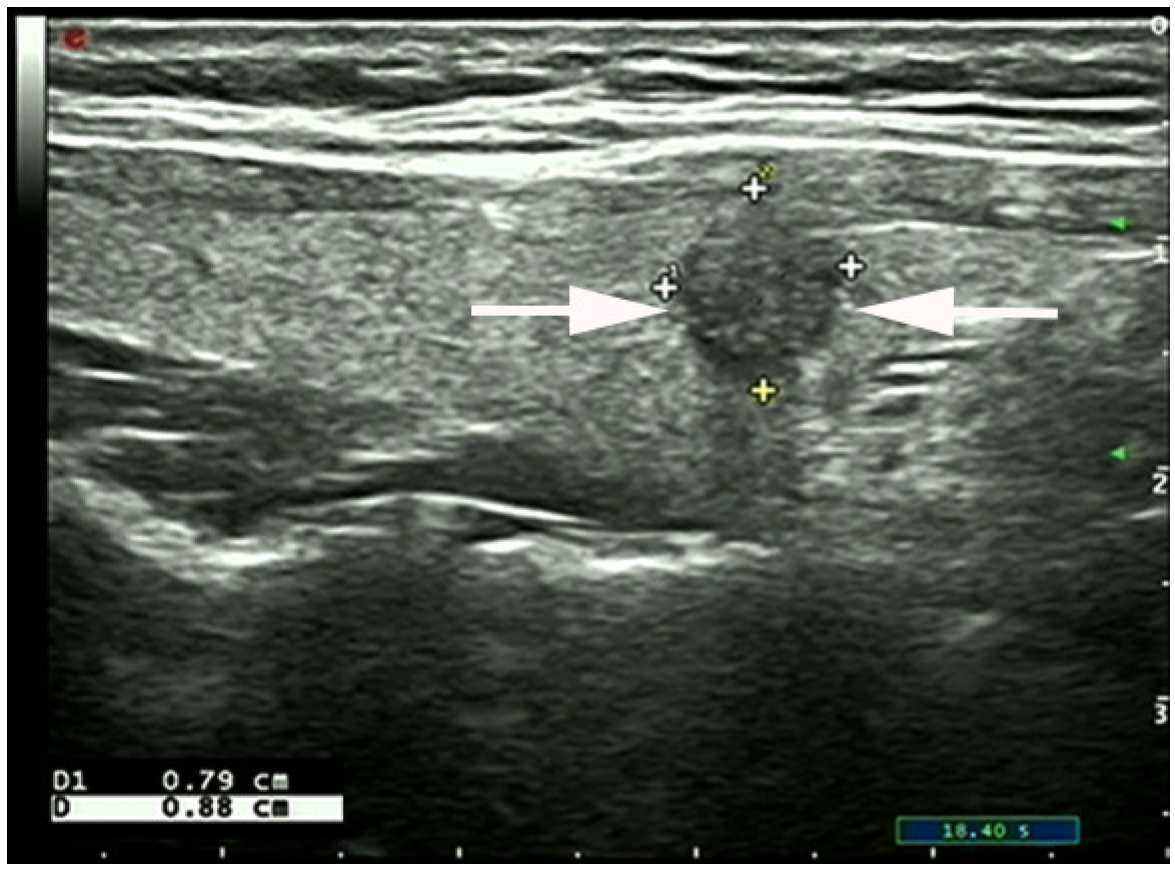

2.2. Ultrasound Imaging

- Chen, S.-P.; Hu, Y.-P.; Chen, B. Taller-Than-Wide Sign for Predicting Thyroid Microcarcinoma: Comparison and Combination of Two Ultrasonographic Planes. Ultrasound Med. Biol. 2014, 40, 2004–2011. [Google Scholar] [CrossRef]

- Kwak, J.Y.; Kim, E.-K.; Youk, J.H.; Kim, M.J.; Son, E.J.; Choi, S.H.; Oh, K.K. Extrathyroid Extension of Well-Differentiated Papillary Thyroid Microcarcinoma on US. Thyroid 2008, 18, 609–614. [Google Scholar] [CrossRef]

- Moon, S.J.; Kim, D.W.; Kim, S.J.; Ha, T.K.; Park, H.K.; Jung, S.J. Ultrasound assessment of degrees of extrathyroidal extension in papillary thyroid microcarcinoma. Endocr Pract. 2014, 20, 1037–1043. [Google Scholar] [CrossRef]

- Chung, S.R.; Baek, J.H.; Choi, Y.J.; Sung, T.Y.; Song, D.E.; Kim, T.Y.; Lee, J.H. Sonographic Assessment of the Extent of Extrathyroidal Extension in Thyroid Cancer. Korean J. Radiol. 2020, 21, 1187–1195. [Google Scholar] [CrossRef]

- Jeong, S.Y.; Chung, S.R.; Baek, J.H.; Choi, Y.J.; Sung, T.-Y.; Song, D.E.; Kim, T.Y. Sonographic assessment of minor extrathyroidal extension of papillary thyroid micro-carcinoma involving the posterior thyroid capsule. Eur. Radiol. 2022, 32, 6090–6096. [Google Scholar] [CrossRef] [PubMed]